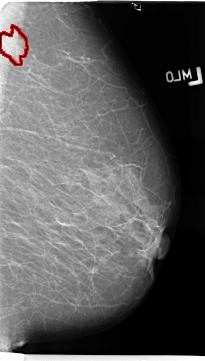

B_3137_1.RIGHT_MLO

LEFT_MLO LINES 4688 PIXELS_PER_LINE 2656 BITS_PER_PIXEL 12 RESOLUTION 50 OVERLAY

FILE: B_3137_1.LEFT_MLO.OVERLAY

TOTAL_ABNORMALITIES 1

ABNORMALITY 1

LESION_TYPE MASS SHAPE IRREGULAR MARGINS SPICULATED

ASSESSMENT 4

SUBTLETY 4

PATHOLOGY MALIGNANT

TOTAL_OUTLINES 1

BOUNDARY